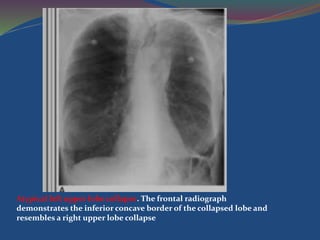

Left Upper Lobe Collapse

Atypical left upper lobe collapse. The frontal radiograph

demonstrates the inferior concave border of the collapsed lobe and

resembles a right upper lobe collapse